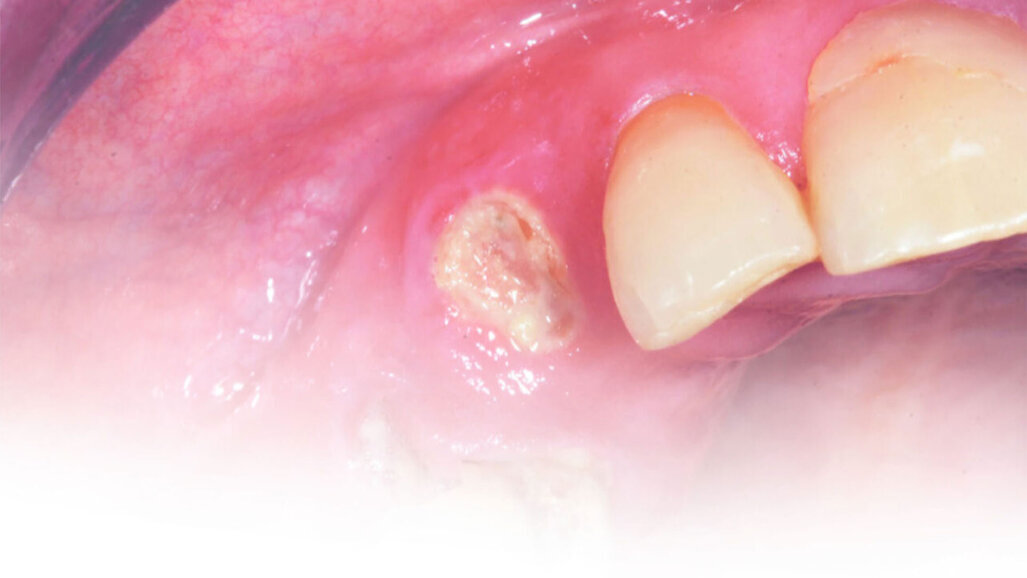

Η θεραπεία του ζωντανού πολφού παίζει βασικό ρόλο στη θεραπεία της νεογιλής οδοντοφυΐας. Η θεραπεία του πολφού, συγκεκριμένα οι πολφοτομές, μπορεί να διατηρήσει ένα νεογιλό δόντι και να αποφύγει πιθανά προβλήματα όπως πόνο, πρήξιμο, μόλυνση και πρόωρη απώλεια δοντιών που μπορεί να οδηγήσει στην ανάγκη για τη διατήρηση του χώρου, ή σε ορισμένες περιπτώσεις σε ακριβότερες οδοντιατρικές θεραπείες όπως η ορθοδοντική.

Το Biodentine™, έχει δείξει ένα δυνατό ιστορικό κλινικών επιτυχών. Το Biodentine ™ (Septodont) είναι ένα υλικό πυριτικού ασβεστίου που περιέχει πυριτικό τριασβέστιο και διασβέστιο, οξείδιο του αργιλίου και χλωριούχο ασβέστιο. Εμφανίζει μια μεγάλη ποικιλία χρήσεων και στη νεογιλή και τη μόνιμη οδοντοφυΐα. Μπορεί να χρησιμοποιηθεί για την έμμεση και άμεση θεραπεία του πολφού, σε πολφοτομές (καθολικές και μερικώς), ακρορριζικές φραγές (apexification), επιδιορθώσεις διατρήσεων και εμφράξεις ριζικού σωλήνα.